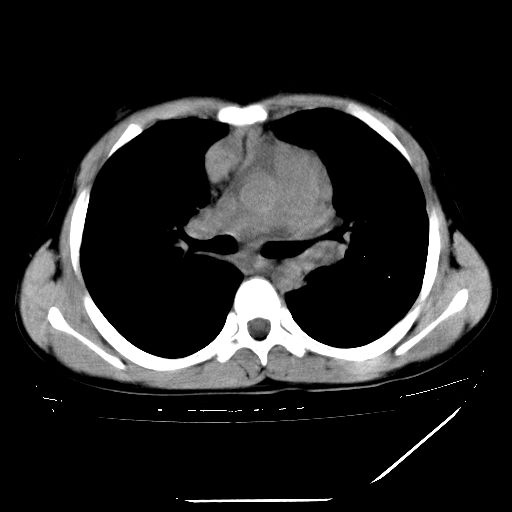

男,13岁,咳嗽、咳痰伴发热一周。

中上纵隔见多枚淋巴结肿大,部分相互融合成团片,左肺门增大,上叶支气管变窄,肺内多处斑片状 索条状及棉絮状致密影。临床“男,13岁,咳嗽、咳痰伴发热一周。”首先考虑:原发综合征!不除外淋巴瘤可能!

纵隔多发肿大淋巴结,部份有融合改变。双肺血管气管束增厚,以肺门为中心向外周散发,以左肺下叶为明显。考虑淋巴瘤可能性大。不除外原发综合征。

中上纵隔见多枚淋巴结肿大,部分相互融合成团片,左肺门增大,上叶支气管变窄,左肺支气管血管束增粗,可见磨玻璃样影。临床“男,13岁,咳嗽、咳痰伴发热一周。”首先考虑:淋巴瘤可能性大!

淋巴瘤可能性大并肺部侵犯。

中上纵隔见多枚淋巴结肿大,部分相互融合成团片,纵隔内脂肪间隙模糊,左肺门增大,上叶支气管变窄,左肺支气管血管束增粗,可见磨玻璃样影。考虑纵隔淋巴管炎